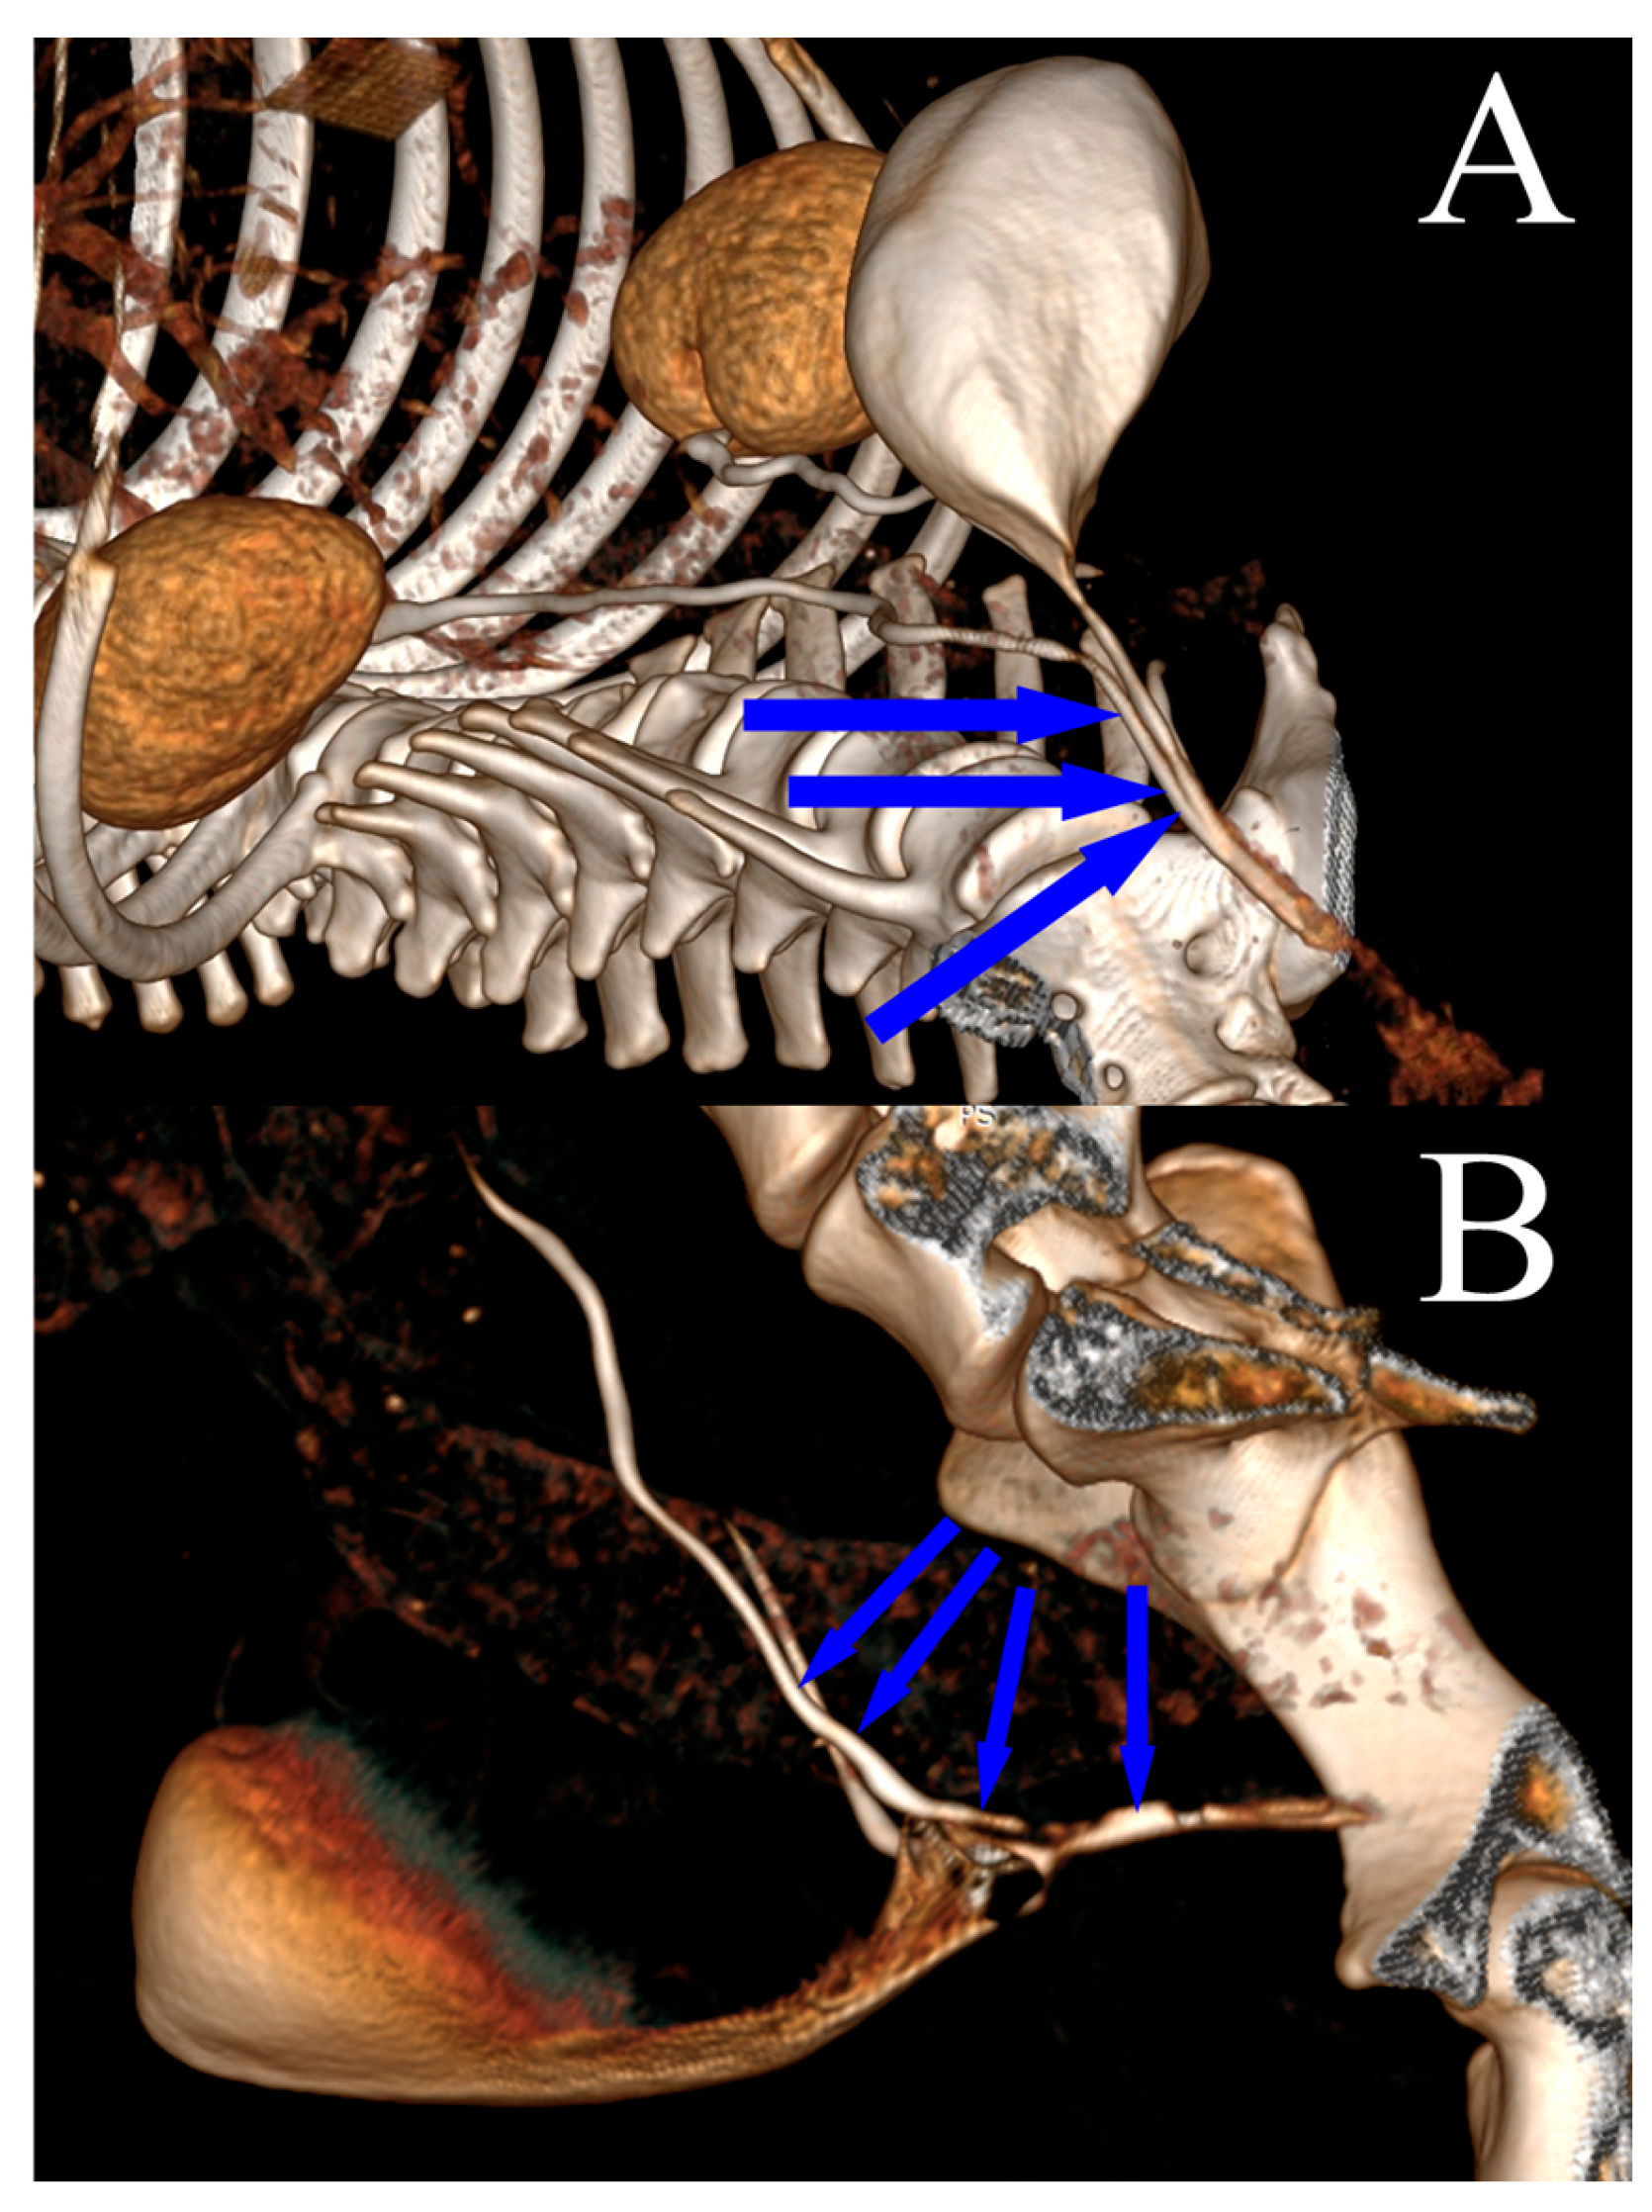

Complete blood tests (hematological and biochemical), urinalysis, and urine cultures were carried out prior to diagnostic imaging. In the diagnostic examination, diagnostic images, including native and contrast-enhanced computed tomography (CT) images of the abdomen and genitourinary system, were collected (Figure 1A,B).

Figure 1. Computed tomography visualization (3D reconstruction) of the ectopic ureter course in a female dog after the administration of intravenous contrast. The blue arrows indicate the course of the ectopic ureter: (A) extramural ectopia; (B) intramural ectopia.